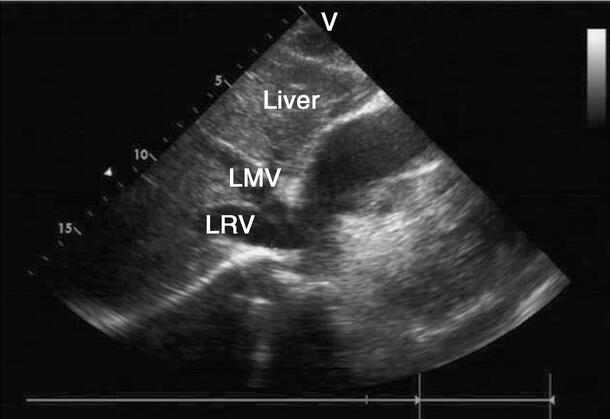

超声图片 如图2‐1‐220。

图2‐1‐220 中‐大量心包积液

A﹒左室长轴切面;B﹒心尖四腔心切面;PE:心包积液

超声描述 心脏各房室腔内径正常。升主动脉及主肺动脉内径正常。左室壁厚度正常,静息状态下未见节段性室壁运动异常,左室整体收缩功能正常。各瓣膜形态结构及启闭正常。心包腔内可见中~大量液性暗区。下腔静脉略增宽,塌陷指数略减低。各瓣膜血流频谱速度随呼吸变化幅度略有改变。

超声诊断 中~大量心包积液;下腔静脉略增宽,塌陷指数略减低。